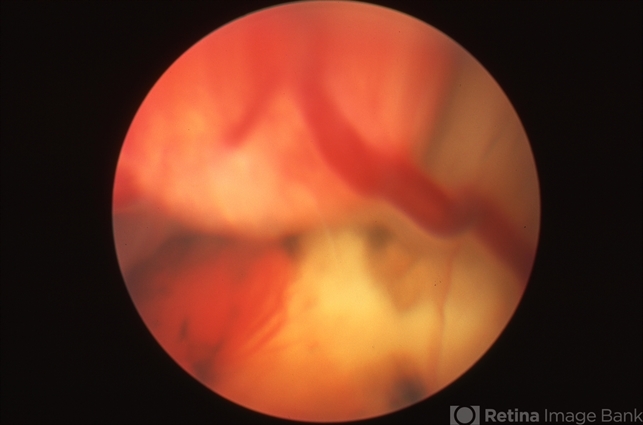

- Von Hippel-Lindau, retinal angioma

- Fundus camera

- 20-year-old patient with a peripheral retinal angioma OS and dilated feeder vessel secondary to Von Hippel-Lindau.